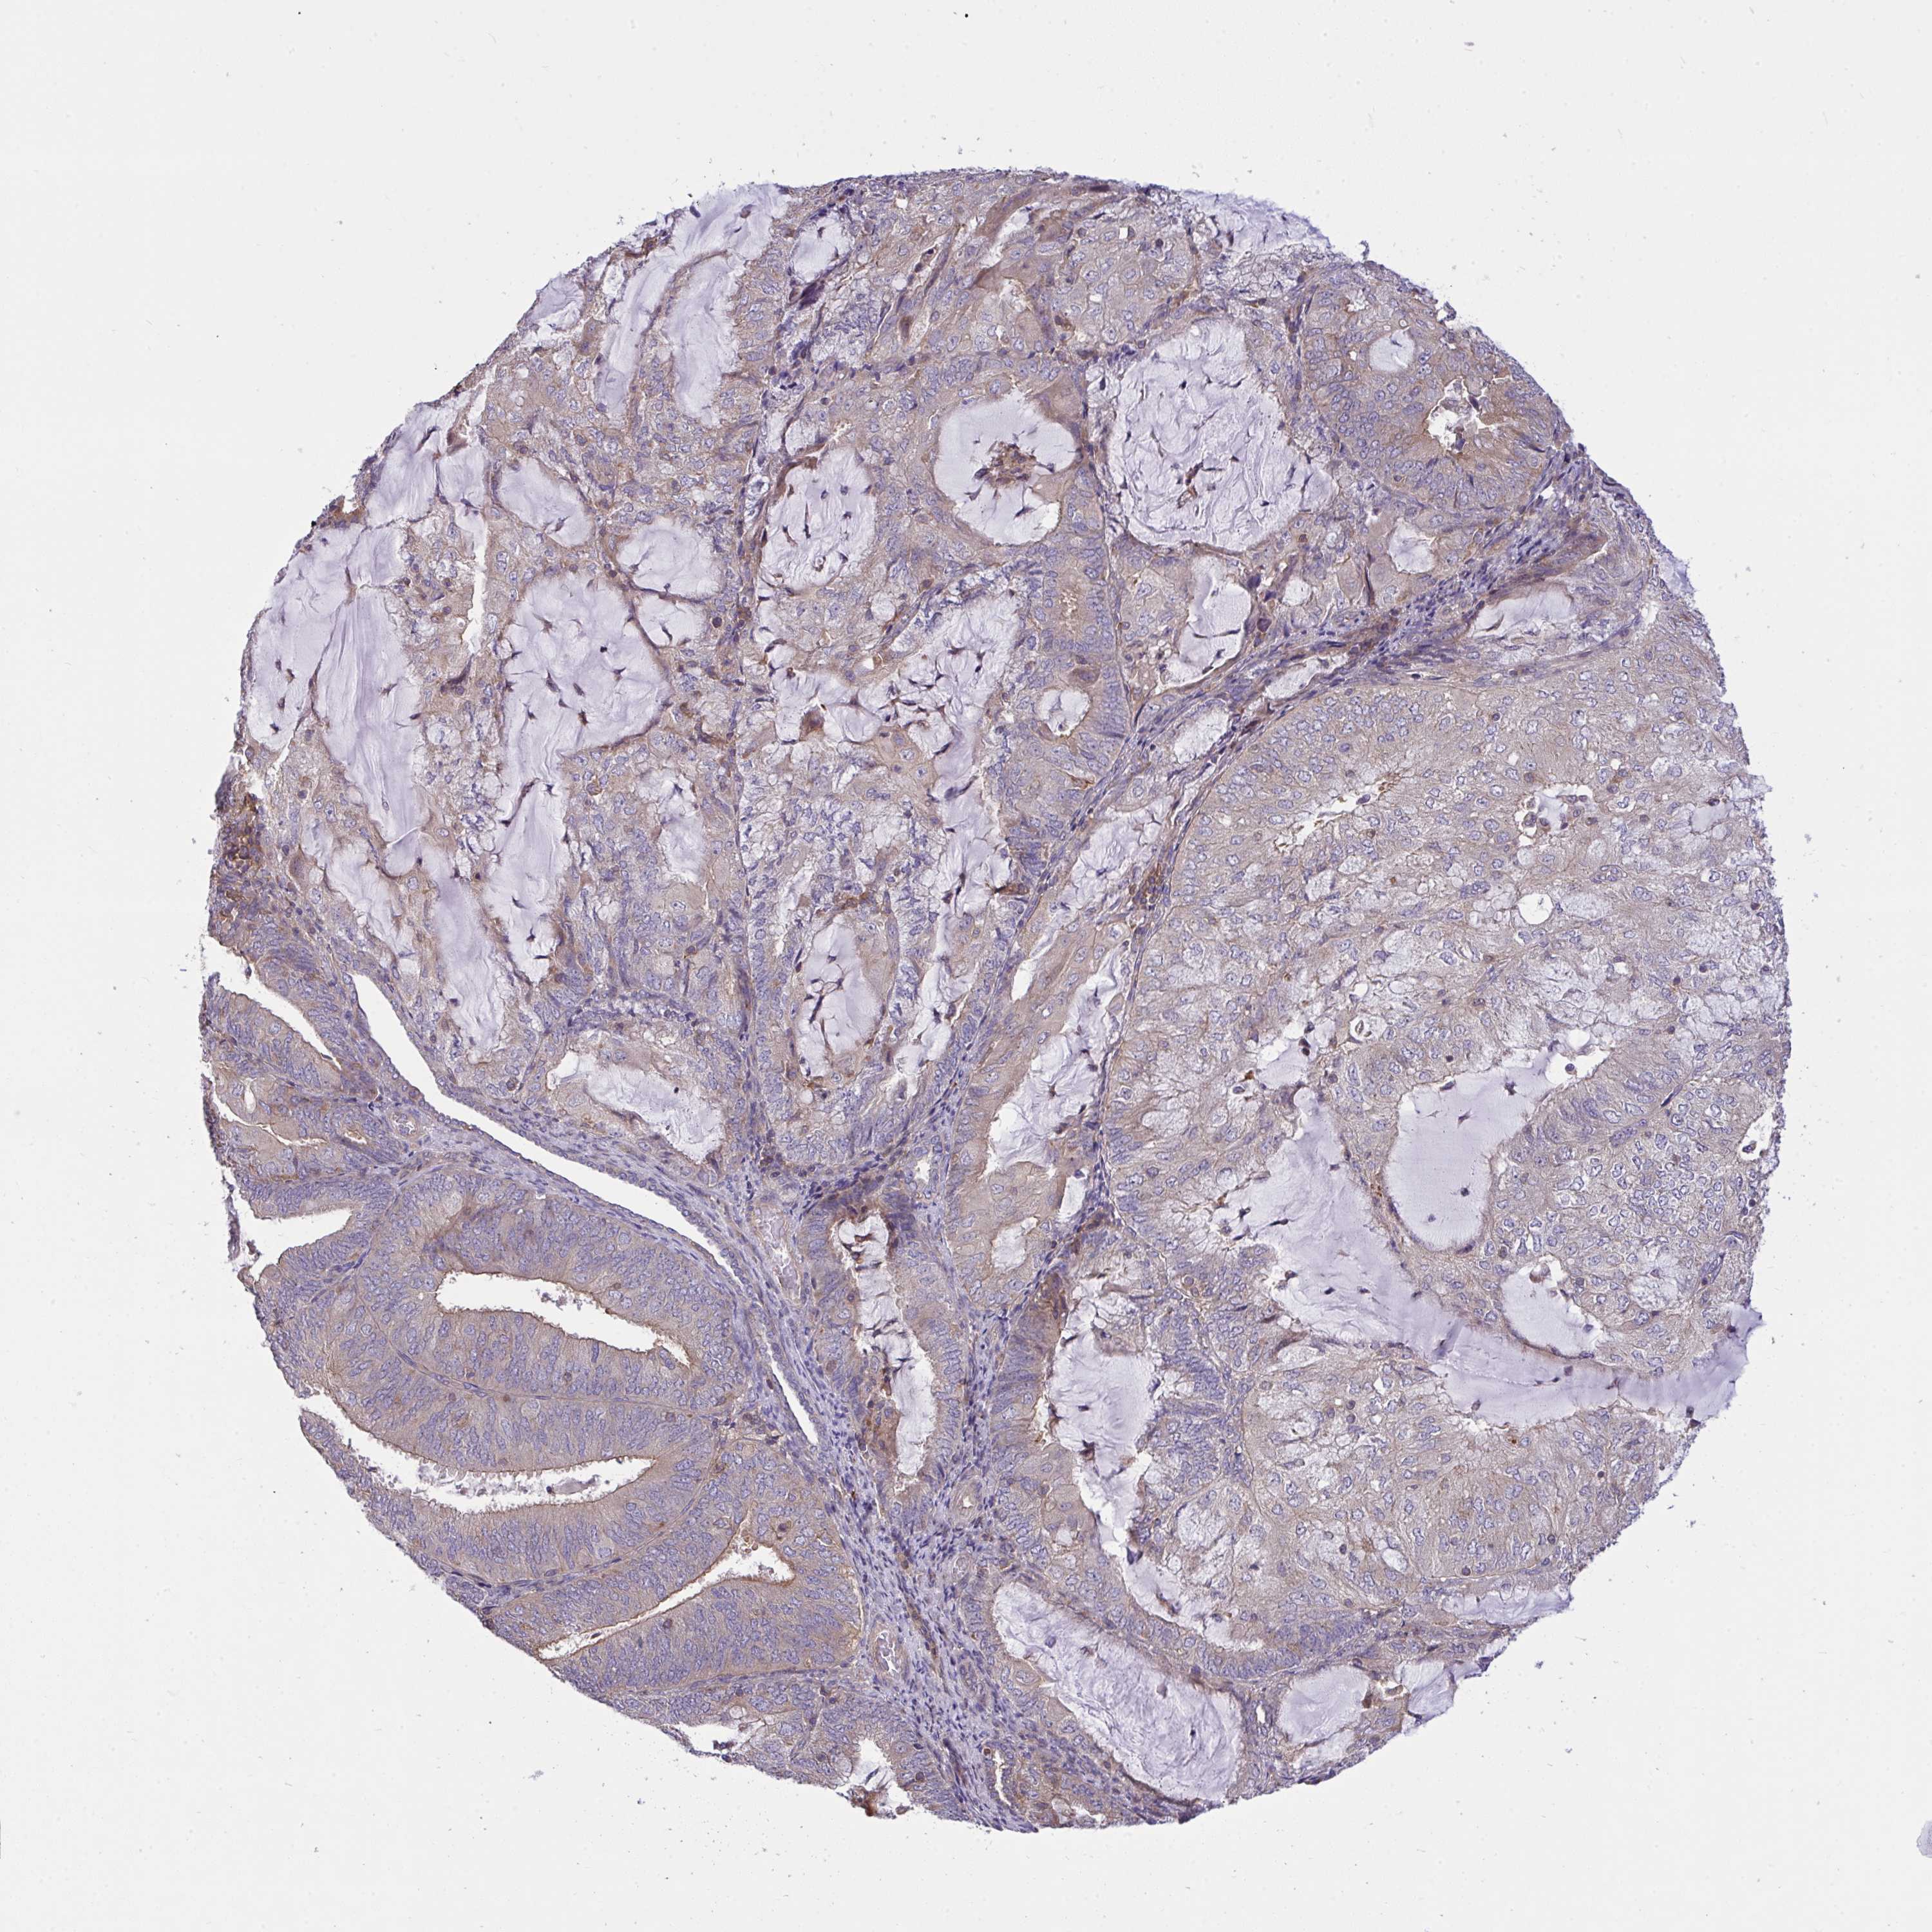

ENDOMETRIAL CANCER - Protein expressioni

A mouse-over function shows sample information and annotation data. Click on an image to view it in a full screen mode. Samples can be filtered based on level of antibody staining by selecting one or several of the following categories: high, medium, low and not detected. The assay and annotation is described here.

Note that samples used for immunohistochemistry by the Human Protein Atlas do not correspond to samples in the TCGA dataset.

Antibody stainingi

Antibody staining in the annotated cell types in the current human tissue is reported as not detected, low, medium, or high, based on conventional immunohistochemistry profiling in selected tissues. This score is based on the combination of the staining intensity and fraction of stained cells.

Each image is clickable and will lead to virtual microscopy that enables deeper exploration of all samples and also displays staining intensity scores, fraction scores and subcellular localization as well as patient and tissue information for each sample.

Antibody HPA035053

Antibody CAB022294

Staining

High

Medium

Low

Not detected

Intensity

Strong

Moderate

Weak

Negative

Quantity

>75%

75%-25%

<25%

None

Location

Nuclear

Cytoplasmic/membranous

Cytoplasmic/membranous,nuclear

Adenocarcinoma, NOS